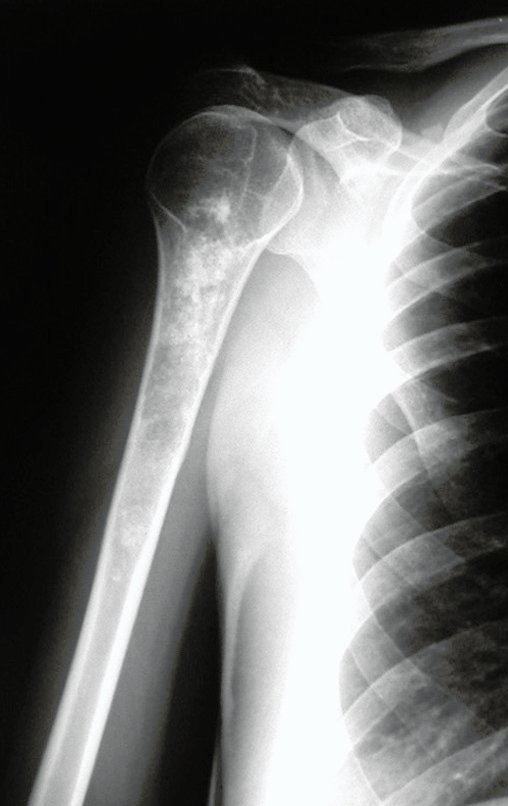

Chondrosarcoma occurs in bones of endochondral origin, mainly in the roots of the limbs: shoulder (Figures 1 to 3), pelvis (Figures 4 to 10), ribs and axial skeleton 1 , being rare in bones of membranous origin 11,14,15 ,24.

Figures 1 to 10 illustrate large chondrosarcomas of the shoulder girdle and pelvic girdle, which evolved slowly.